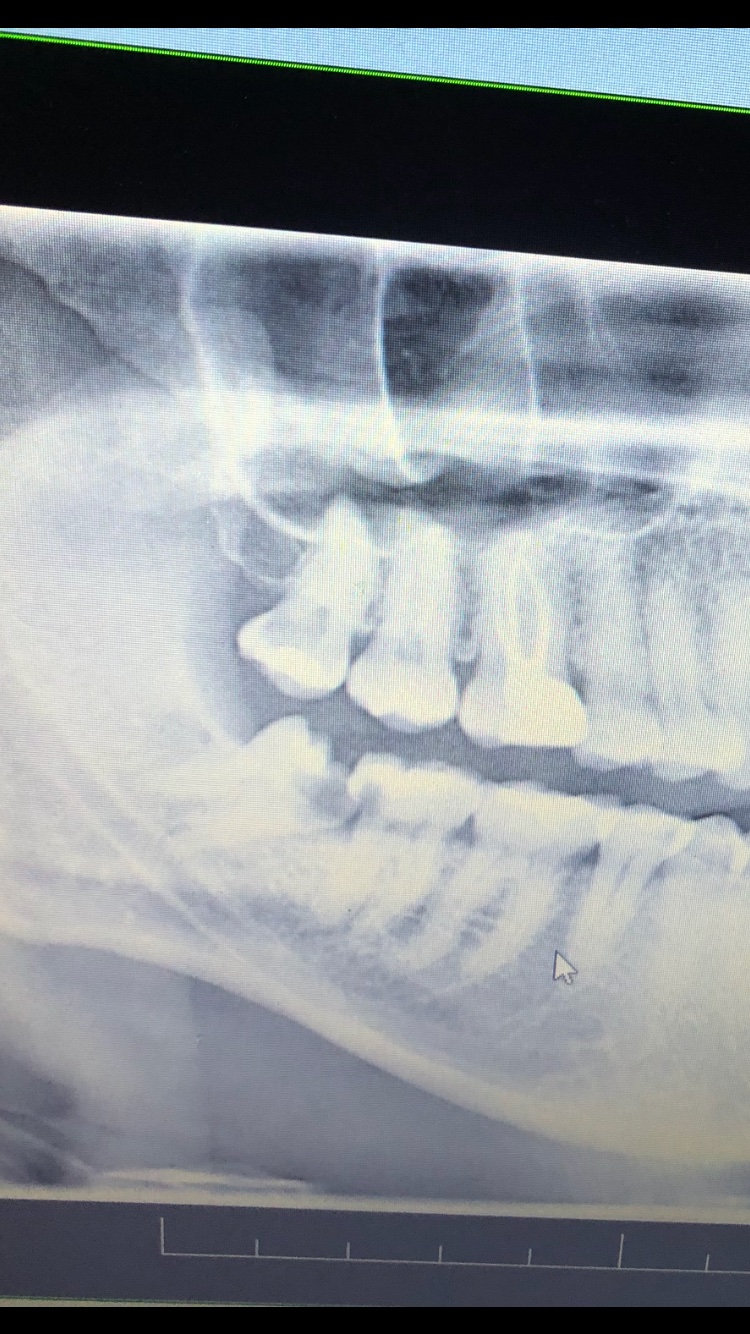

Trhanie ležiaceho zuba múdrosti: Čo očakávať?